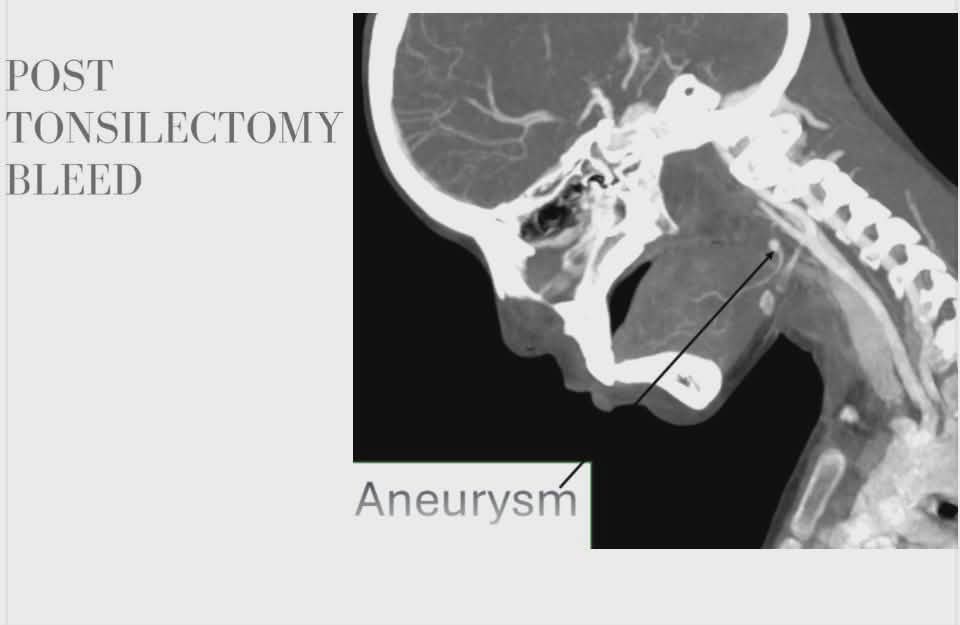

نجح فريق طبي متخصص بمستشفيات سوهاج الجامعية في إنقاذ حياة طفلة تبلغ من العمر 12 عاماً، عقب إصابتها بمضاعفات خطيرة ونزيف حاد ناتج عن تمدد شرياني بالرقبة، وذلك في تدخل دقيق باستخدام الأشعة التداخلية والقسطرة، دون الحاجة لتدخل جراحي تقليدي.

وصلت الطفلة إلى المستشفى الجامعي في حالة حرجة تعاني من قيء دموي حاد، وذلك بعد خضوعها لعملية استئصال لوزتين خارج المستشفى، تبعها تدخل جراحي فشل للسيطرة على النزيف.

من جانبه، أشار الدكتور محمد نصر الدين حمدون، عميد كلية الطب، إلى أن المستشفى استثمر في أحدث الأجهزة الطبية، إذ تم استخدام جهاز القسطرة ثنائي القطب، وهو الوحيد من نوعه في منطقة جنوب الصعيد، للتعامل مع التمدد الشرياني الموجود في منطقة دقيقة بجدار الحلق.

وأوضح الدكتور أحمد كمال، المدير التنفيذي للمستشفيات، أن وحدة القسطرة نجحت في غلق التمدد الشرياني النازف باستخدام "حلزونات دقيقة" عبر الأشعة التداخلية، مما أوقف النزيف بشكل فوري وآمن، وجنب الطفلة مخاطر الجراحة المفتوحة.